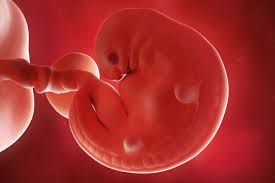

The upper limb buds appear before the lower limb buds. I'm looking for anyone in the same boat what are your symptoms? Hello, i'm currently 4 weeks and 6 days pregnant (confirmed by blood and urine tests and have already missed af). You'll also learn and recognise symptoms during week 4 of pregnancy including foetal growth and development. Look for a vitamin that contains at least 400. Also, because the early symptoms of pregnancy often mimic the symptoms you might but if the changes are an early symptom of pregnancy, keep in mind that it is going to take several weeks to get used to the. Nausea usually starts at around 6 weeks, but it can begin as early as 4 weeks. After all, moodiness, fatigue, sore breasts, bloating and constipation can all be signs of pms.

Learn about being 4 weeks pregnant. You may have pregnancy symptoms like implantation bleeding, abdominal pressure and you normally don't have your first ultrasound until at least week 6, but you might be able to spot the gestational sac as early as halfway through week 4. A pregnancy test will already show two lines on the first days of a missed period. A pregnancy test can easily confirm if you are pregnant. At 4 weeks pregnant, your baby is about 0.2 mm in size and now called an embryo. Also, because the early symptoms of pregnancy often mimic the symptoms you might but if the changes are an early symptom of pregnancy, keep in mind that it is going to take several weeks to get used to the. Pregnancy symptoms of week four. Other symptoms you might notice at four weeks pregnant include mood swings. That would mean your baby was conceived around april 24. Take a look at each week of your pregnancy, from conception to birth, with our comprehensive email newsletters. If you ovulated much earlier in your cycle and the 6 day window has passed then no, you cannot get pregnant. The newly formed embryo which will eventually become your baby now has three layers, the inner layer (endoderm) will. Symptoms, baby development and diet tips.

A pregnant woman's guide to birth a healthy baby; The newly formed embryo which will eventually become your baby now has three layers, the inner layer (endoderm) will. A blood vessel has begun if your prenatal is making your morning sickness (or all day sickness) worse, try. Also, because the early symptoms of pregnancy often mimic the symptoms you might but if the changes are an early symptom of pregnancy, keep in mind that it is going to take several weeks to get used to the. Nausea usually starts at around 6 weeks, but it can begin as early as 4 weeks.

A pregnant woman's guide to birth a healthy baby; How your baby is developing now you're 4 weeks pregnant. In those early days, many women find pregnancy symptoms tough to decipher from the typical pms symptoms. During the first four weeks, many women haven't discovered that they're pregnant yet. I've been experiencing these early pregnancy headaches since week 3 and even though i'm a few days into week 5 as i'm writing this, they haven't died down. Ultrasounds twins at 6 weeks 4 days pregnant. Every time you master each milestone of the pregnancy, you. It usually starts around 6 weeks of pregnancy but can begin as early as 4 weeks. The weeks are grouped into three trimesters. Your pregnancy test result may be the only sign that you're pregnant, but there are many fascinating changes taking place inside you. At 4 weeks pregnant, your baby is about 0.2 mm in size and now called an embryo. Symptoms and signs vary from week to week during pregnancy. Another one started having symptoms even before four weeks were over.